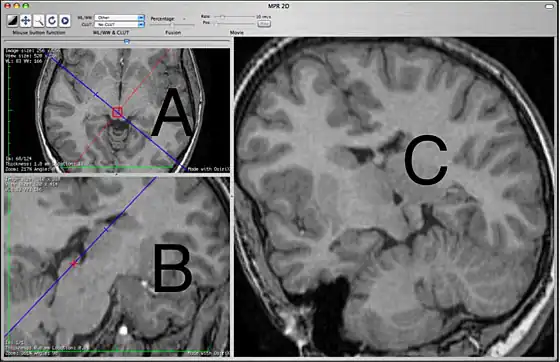

The 2D MPR window

This 2D MPR Viewer allows generating a MPR slice in any position and orientation through the 3D volume. This mode shows three viewing ports. In the picture above, the two on the left are labeled A and B. The third, on the right, is labeled C.

The primary purpose of the A and B view ports is to specify the plane that will be shown in the C view port. The A and B view ports are partially obscured by lines used specify the plane to be seen in C. These lines cannot be hidden. In this sense, the C view port is designed for diagnostic viewing and the other two view ports are primarily to specify what is to be shown in C. The view ports are not all equal, which may be different from what users of other MPR interfaces are expecting. View port A shows a blue line which corresponds to the orientation of what is being seen in C and also contains a red line that corresponds to what is seen in B. View port B shows only a blue line that also corresponds to what is seen in C. View port C has no lines.

The specifying view port A will show the original images in the plane that they were originally acquired, most commonly the axial plane. You can scroll through these images to choose the one that you want to work off. The specifying view port B shows planes that are orthogonal to view port A. If A is showing an axial image then on initially opening the 2D MPR Viewer, B will show a sagittal image. The specific orthogonal plane that is being created in B is indicated in the A view port as a red line. Under these initial circumstances, C will be showing a coronal reconstruction that corresponds to the blue line.

If you are interested in seeing a sagittal image, one can simply look at the B view port but this is not really what a specifying view port is for. The specifying view ports are smaller and obscured by lines. To see a clean sagittal image, you want to grab the blue line in view port A and swing it 90 degrees. At this point, the C view port will show a sagittal image. The red line, indicating the plane of view port B, will maintain itself perpendicular to the blue line. This line, indicating the orientation of view port B, will now be documenting the coronal plane that is visible in B. You cannot grab the red line to do this rotation. Only the blue line can be grabbed. You can move the intersection of the two lines by grabbing within the red circle. This will center the point of rotation